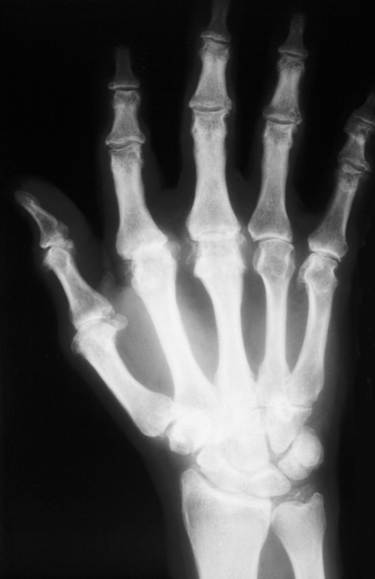

MCP OA in a young person = think HEMOCHROMATOSIS